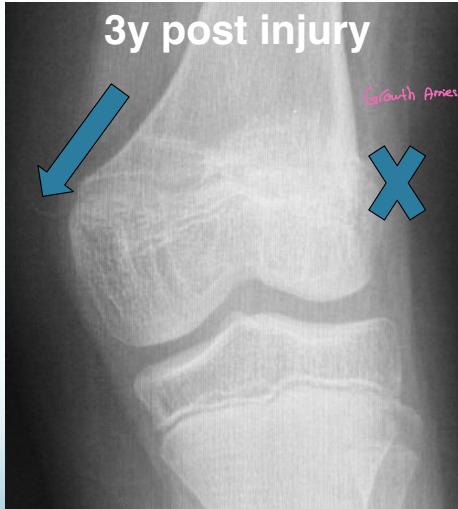

Injured and uninjured wrists after premature physeal closure

Asymmetrical Physeal Affection

- Seen on x-ray

- One side grows more than the other

- Causing an increasing deformity

- Oblique Park-Harris growth arrest/recovery line (white arrows)